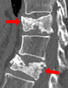

転移した部位に、5日間に計5回の放射線治療をします。黄色から赤色の部分にかけて=図2=強く放射線が当たっています。放射線治療の2年後には、骨の再石灰化が見られます=図3=(赤い矢印部分に新たな石灰化)。それと同時に痛みが減り、鎮痛薬も減らすことができます。効果は半年ぐらいですが、亡くなるまで、痛みがぶり返さなかった患者もたくさんいます。ほとんどが通院で治療ができ、1回10分ぐらいで済みます。治療日数は、病院までの距離や交通手段、サポートしてくれる人の有無などを考えて、1~10回となります。